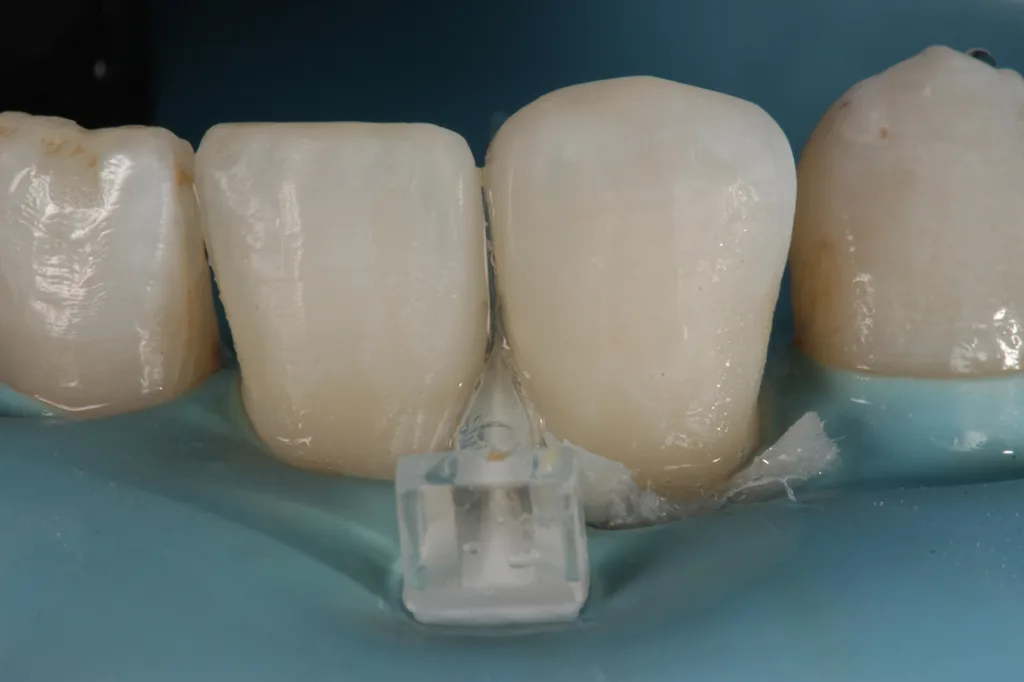

Nach Befundaufnahme und professioneller Zahnreinigung wurde ein CMD-Kurzscreening durchgeführt und ein Fotostatus erstellt. Ein intraorales Mock-up [2] wurde auf Wunsch der Patientin und aus Kostengründen nicht angefertigt. Definitive Versorgung Adhäsivrestaurationen mit Komposit an 31/32 zum Schluss des Diastema laterale (Abb. 3 bis 9).

Grundsätzlich stand die Diskussion einer Gesamtsanierung (Austausch der insuffizienten Zirkonkronen aufgrund von Randspalten/Sekundärkaries, Entfernung retinierte 8er) im Raum. Die Patientin wünschte sich jedoch lediglich den Diastemaschluss im seitlichen UK-Frontzahnbereich und entschied sich nach Abwägung sowohl ethischer als auch finanzieller Aspekte vorerst nur für die Korrektur/Verbesserung der Zahnstellung im Unterkiefer mit direkten freihändig geschichteten Kompositaufbauten an 31 und 32. Konservierende (Füllungstherapie, In-Office-Bleaching), kieferorthopädische (Alignertherapie) und prothetische (Austausch der Zirkonkronen 13 bis 23) Maßnahmen hat sie aus finanziellen Überlegungen vorerst zurückgestellt [3,4].